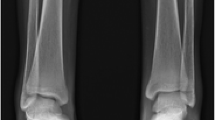

Early fusion of epiphysis

Another common musculoskeletal finding affecting tubular bones is early fusion of the epiphysis, especially in patients who started blood transfusions at a later age. This finding was initially reported in 1964 by Currarino and Elrandson on radiographs of thalassemia patients [29]. This abnormality is mainly seen in children older than 10 years of age. The overall prevalence is thought to be 10–15% in patients with thalassemia major and approximately 23% in patients greater than 10 years old. The most common site for premature fusion of epiphysis is the proximal humeral physis. Distal femur, tibia, fibula, and proximal femur are the next common sites of early fusion [4, 13].

Unilateral or bilateral epiphyseal fusion leads to growth retardation and subsequent short stature, short limb length, and limb discrepancy (Fig. 11). It also results in skeletal deformity secondary to irregular fusion of growth plates and subsequent angulation and deviation of the epiphyses. The most common deformity is the varus deformity of the humerus [20]. In patients with thalassemia major and open growth plates, irregularity across the physis is a marker of early fusion followed by bony bridges across the physis [4].

A 12-year-old male with β-thalassemia major. a Lateral leg radiograph shows early fusion of the epiphysis at the distal tibia. b Lateral knee radiograph in the same patient demonstrates epiphyseal fusion of the distal femur and proximal tibia. Note the diffuse demineralization and thinning of the cortices